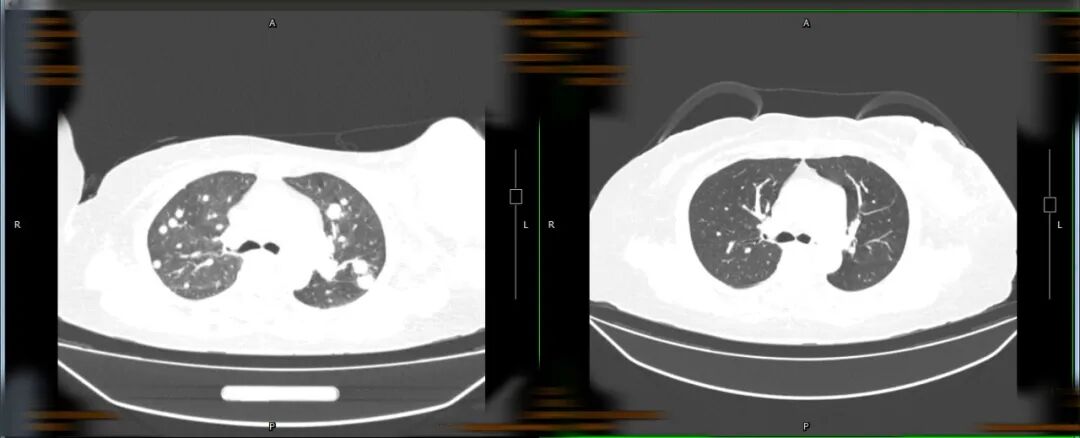

王婆婆2022年7月2日入院

与2023年7月19日左侧乳腺肿瘤CT对比